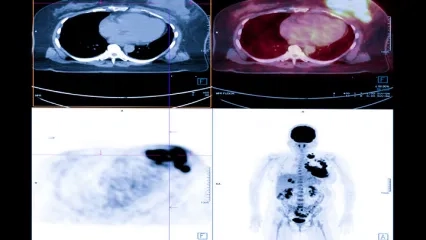

Diagnosis of Heart and Brain Diseases with PET CT

Nuclear Medicine Diagnosis and Imaging